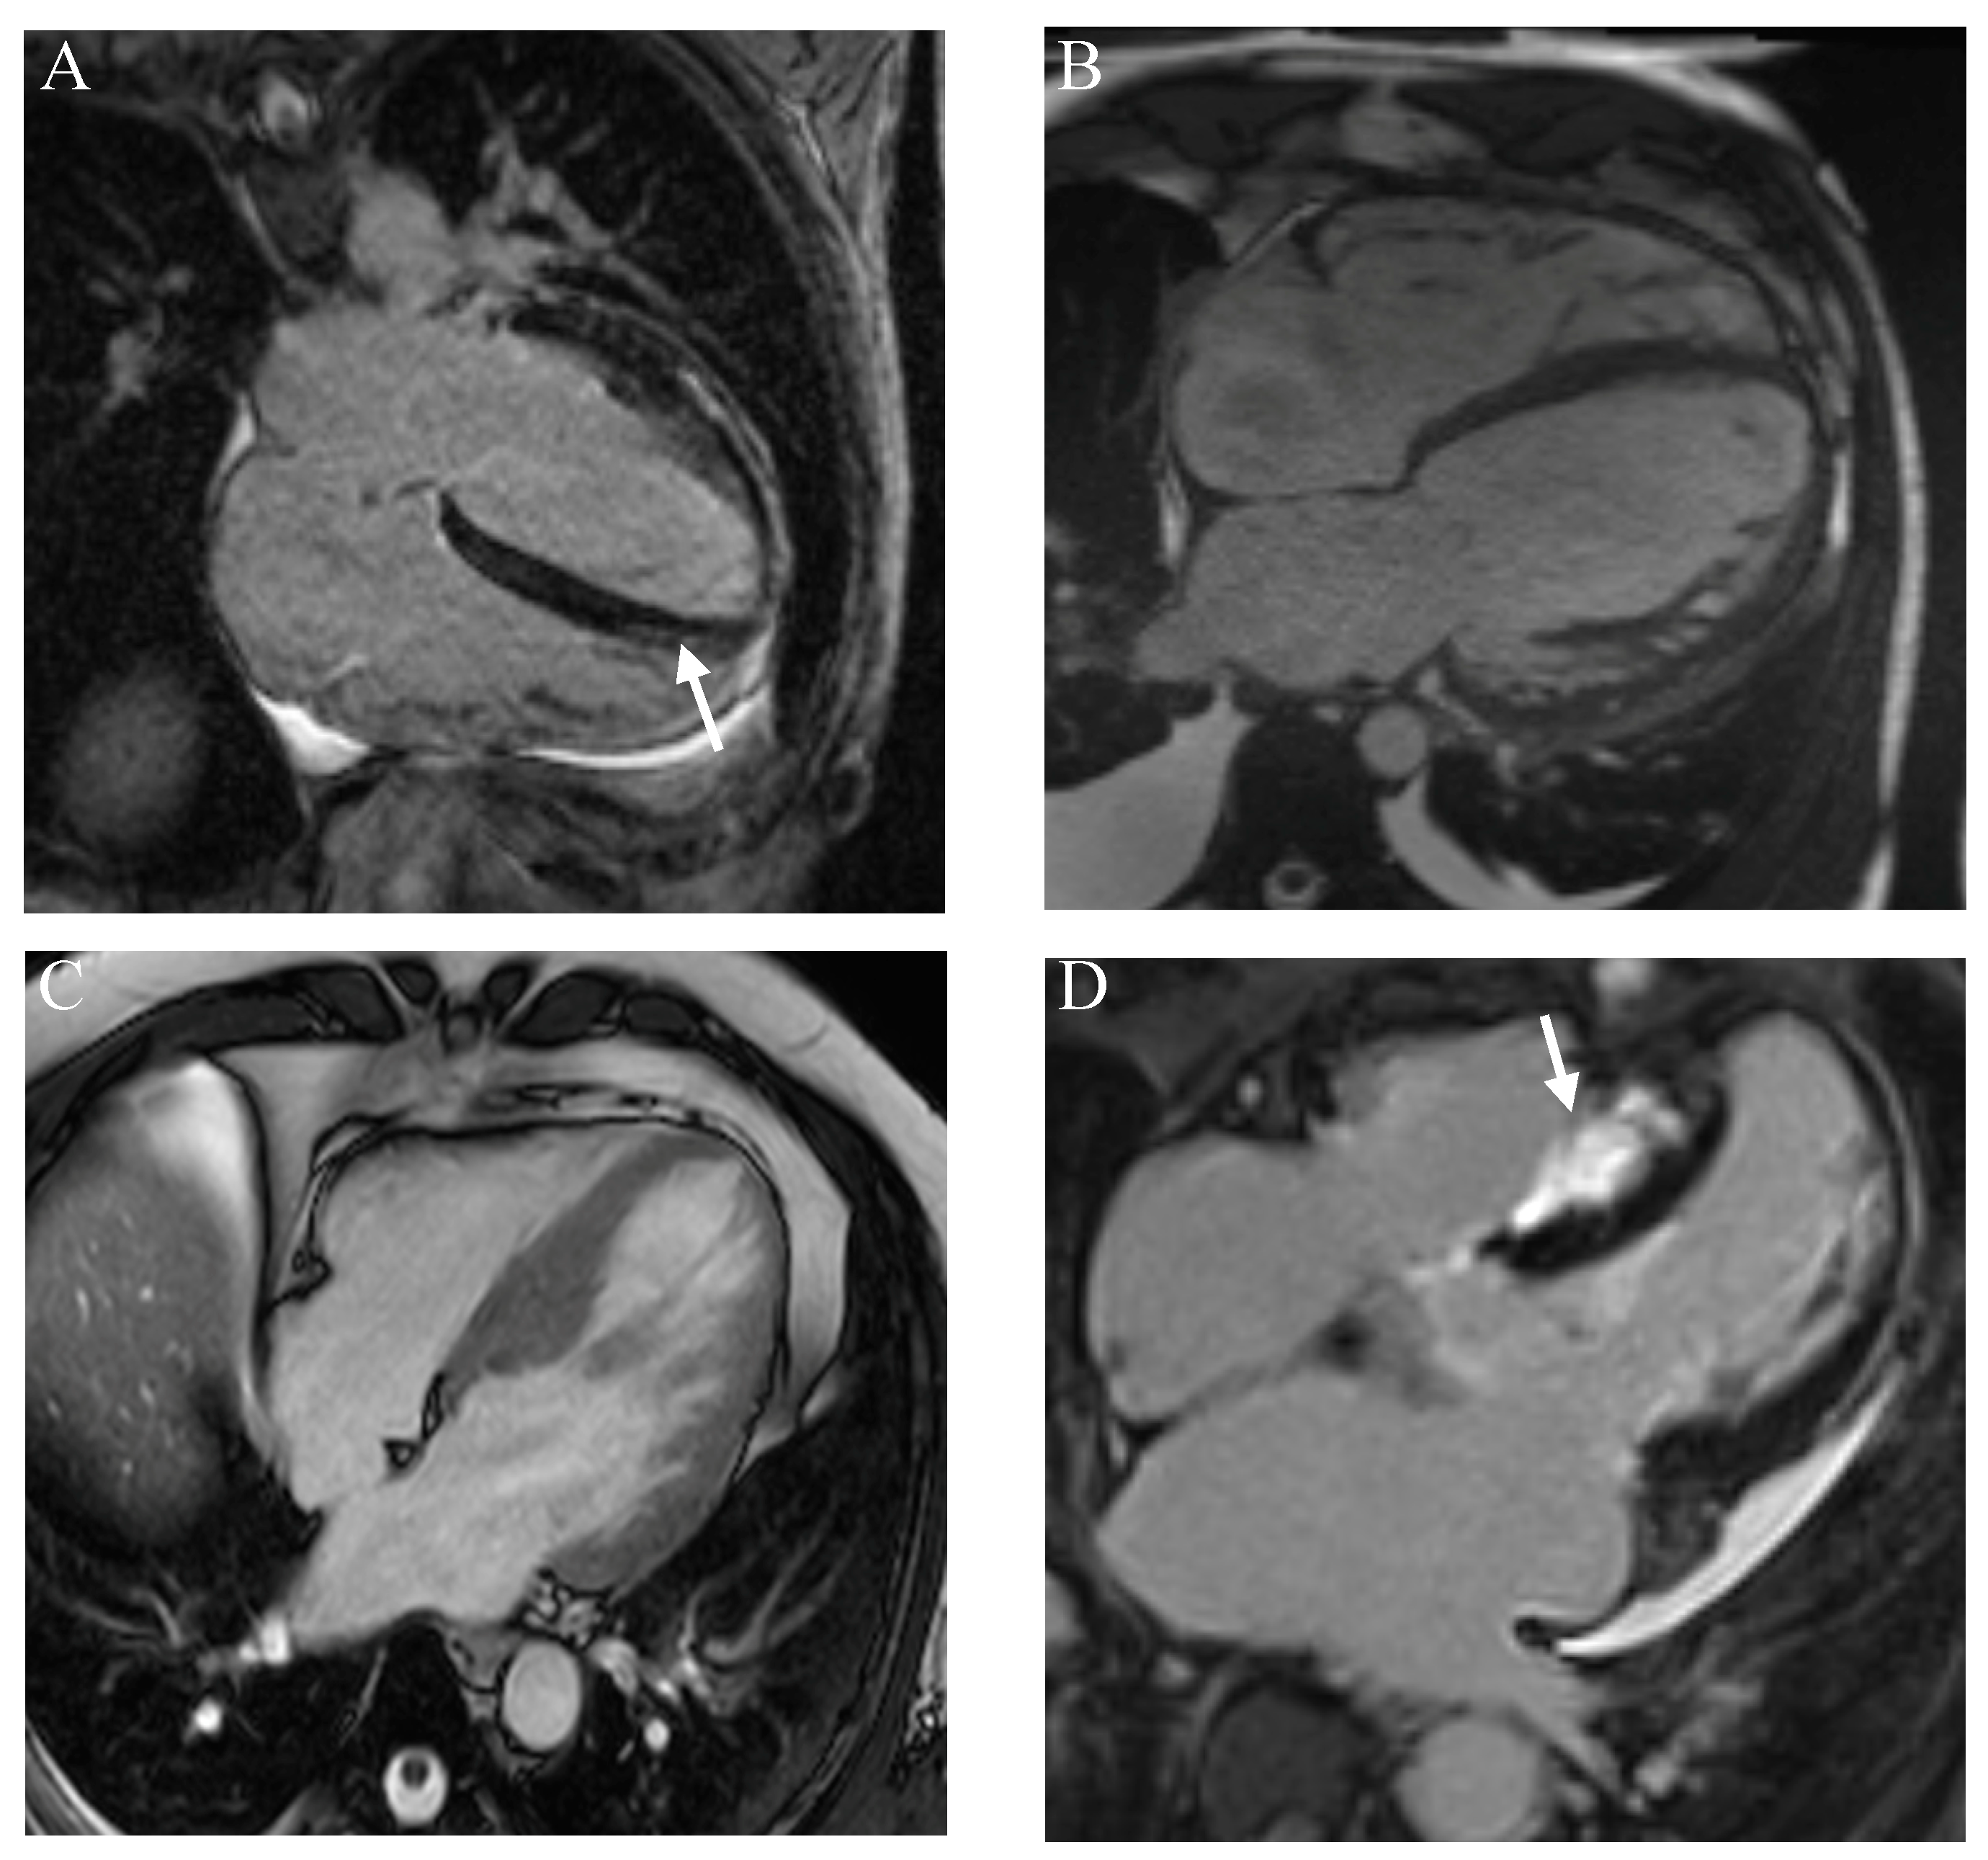

- Marschner, C.A.; Aloufi, F.; Aitken, M.; Cheung, E.; Thavendiranathan, P.; Iwanochko, R.M.; Balter, M.; Moayedi, Y.; Duero Posada, J.; Hanneman, K. Combined FDG PET/MRI versus Standard-of-Care Imaging in the Evaluation of Cardiac Sarcoidosis. Radiol. Cardiothorac. Imaging 2023, 5, e220292. [Google Scholar] [CrossRef]

- Kurashima, S.; Kitai, T.; Xanthopoulos, A.; Skoularigis, J.; Triposkiadis, F.; Izumi, C. Diagnosis of cardiac sarcoidosis: Histological evidence vs. imaging. Expert. Rev. Cardiovasc. Ther. 2023, 21, 693–702. [Google Scholar] [CrossRef]

- Hervier, E.; Glessgen, C.; Nkoulou, R.; François Deux, J.; Vallee, J.P.; Adamopoulos, D. Hybrid PET/MR in Cardiac Imaging. Magn. Reson. Imaging Clin. N. Am. 2023, 31, 613–624. [Google Scholar] [CrossRef]

- Shrivastav, R.; Hajra, A.; Krishnan, S.; Bandyopadhyay, D.; Ranjan, P.; Fuisz, A. Evaluation and Management of Cardiac Sarcoidosis with Advanced Imaging. Heart Fail. Clin. 2023, 19, 475–489. [Google Scholar] [CrossRef]

- Dweck, M.R.; Abgral, R.; Trivieri, M.G.; Robson, P.M.; Karakatsanis, N.; Mani, V.; Palmisano, A.; Miller, M.A.; Lala, A.; Chang, H.L.; et al. Hybrid Magnetic Resonance Imaging and Positron Emission Tomography with Fluorodeoxyglucose to Diagnose Active Cardiac Sarcoidosis. JACC Cardiovasc. Imaging 2018, 11, 94–107. [Google Scholar] [CrossRef]

- Pöyhönen, P.; Nordenswan, H.K.; Lehtonen, J.; Syväranta, S.; Shenoy, C.; Kupari, M. Cardiac magnetic resonance in giant cell myocarditis: A matched comparison with cardiac sarcoidosis. Eur. Heart J. Cardiovasc. Imaging 2023, 24, 404–412. [Google Scholar] [CrossRef]